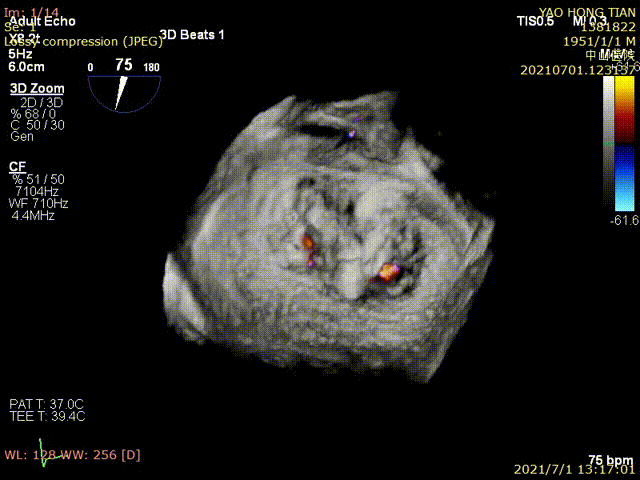

Figure 1 shows a patient's preoperative and postoperative images

Preoperative ultrasound

Postoperative ultrasound